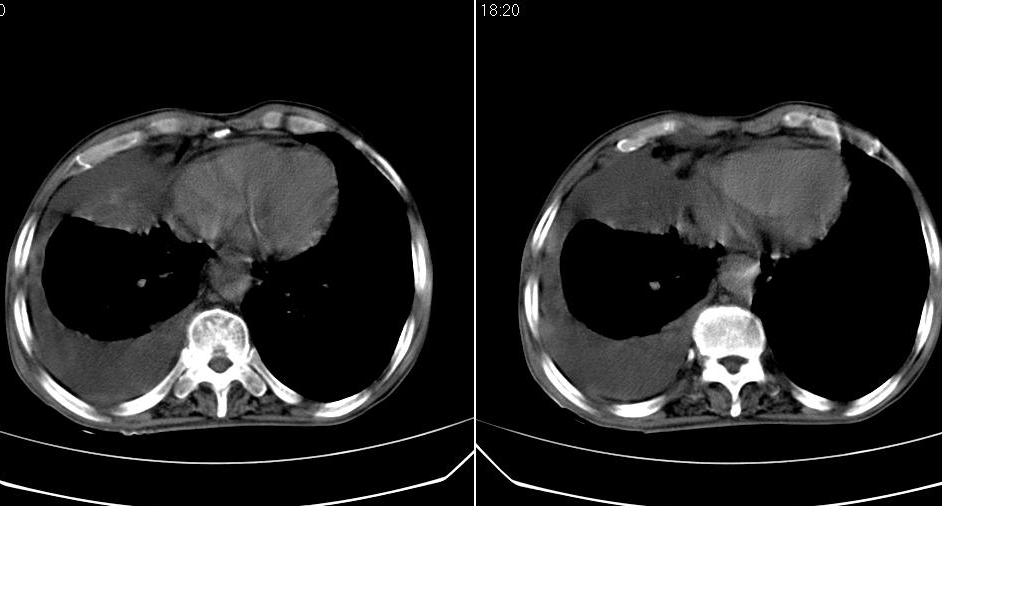

以下是引用zsl6918在2008-5-3 19:53:00的发言:[br]右肺中心型肺癌并纵隔淋巴结转移,胸膜转移,右肺癌性淋巴管炎。

以下是引用liuyue在2008-5-3 20:49:00的发言:[br]1.右侧中心型肺癌伴双肺转移瘤、纵隔淋巴结转移、右侧胸腔积液(侵及胸膜所致可能性大)。[br]2.右肺阻塞性肺炎,癌性淋巴管炎不除外。

以下是引用mzh123在2008-5-3 21:12:00的发言:[br]本人持有不同观点[br]1、右肺似有团块表现,但只有一个层面,所以本人认为还是以片为主,所以不能首先考虑肿瘤[br]2、右肺普遍成纤维化改变 并伴有片状炎症改变,和癌性淋巴管炎表现不同[br]3、所以本人认为是间质纤维化伴感染可能大 及胸腔积液